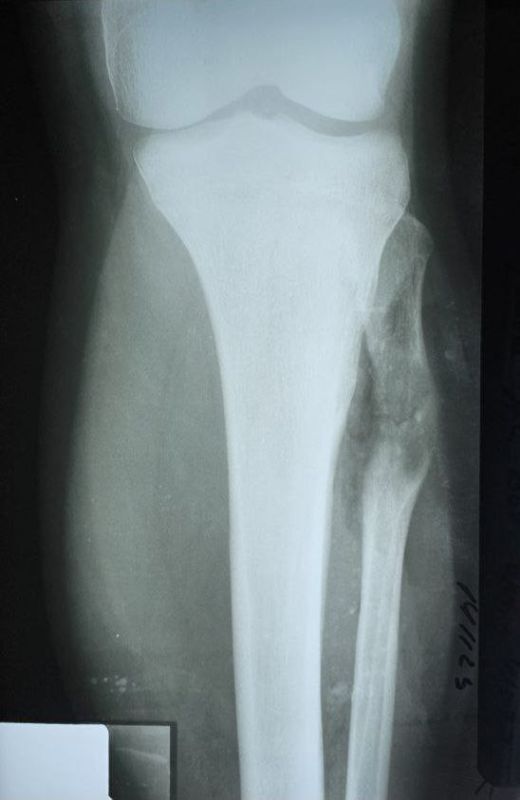

14-летний подросток поступил в Республиканский травматологический центр (РТЦ) Минздрава ДНР с диагнозом «остеохондрома большеберцовой кости».

Опухоль выдавила малоберцовую кость и разорвала соединение большеберцовой и малоберцовой костей.